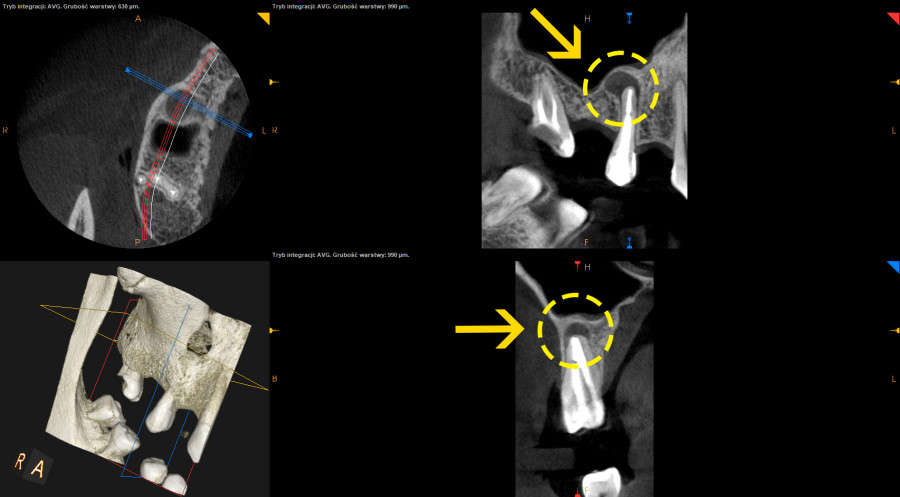

- Po wykonaniu tomografii volumetrycznej zęba 15 stwierdzono rozległą zmianę okołowierzchołkową.

- Przeprowadzono leczenie endodontyczne z użyciem mikroskopu, odbudowę na wkładach z włókna szklanego i zlecono kontrolną tomografię po 6 miesiącach.